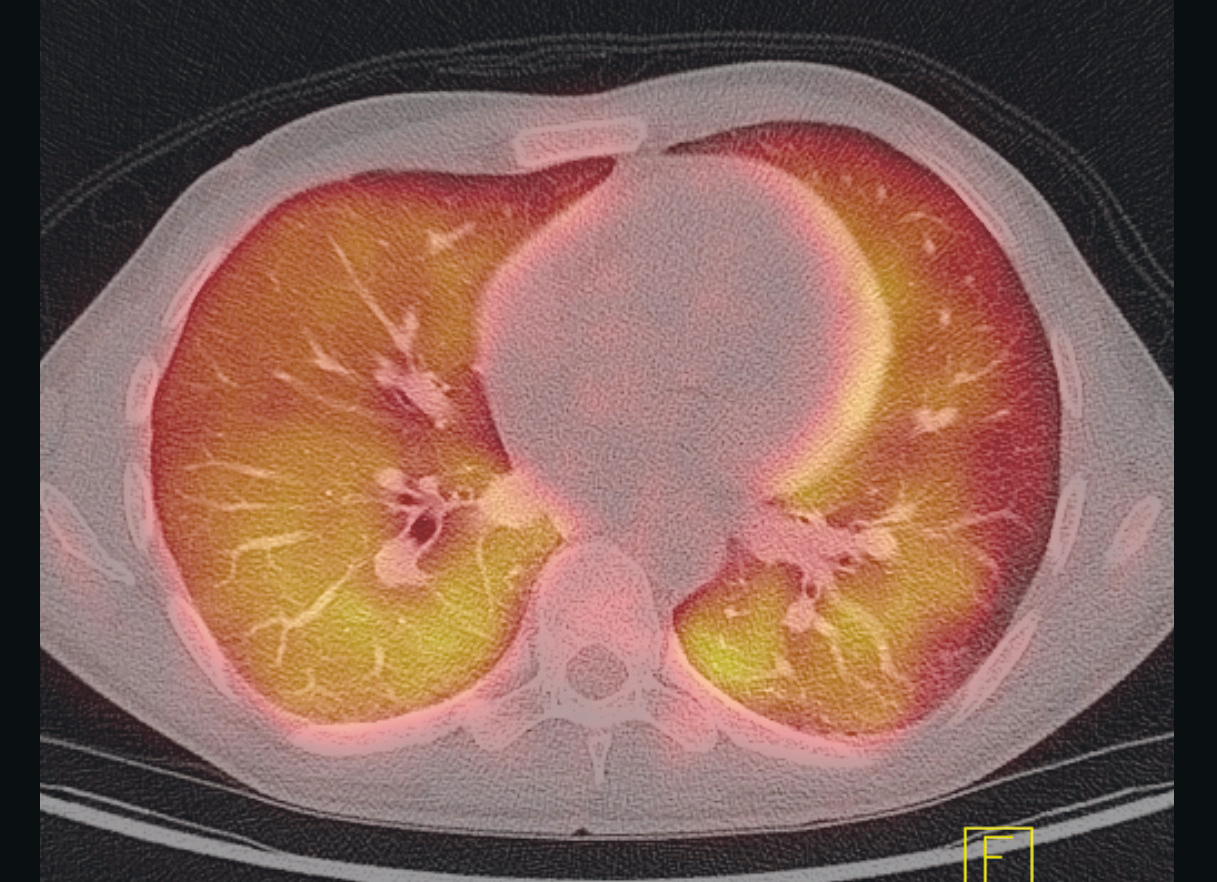

In the days that followed, the patient continued to have episodes of fever and increasing dyspnoea, as well as reduced general condition. PET-CT scan was performed, which showed signs of widespread, diffuse uptake of ¹⁸F-fluorodeoxyglucose (¹⁸F-FDG) in both lungs, as well as reactive spleen and bone marrow (Figure 1).

PET-CT is a modality that combines PET and multislice CT. The most common marker is radioactive ¹⁸F-FDG, a glucose analogue that functions as a marker for metabolic activity in tissue. The PET detector records where the ionising radiation is concentrated in the body, and this is correlated with the anatomic structures on the CT images. Increased ¹⁸F-FDG uptake on PET-CT may be seen, for example, with increased cell division in malignant tumours, and with increased activity in leukocytes in the case of infections and non-infectious inflammatory disorders.